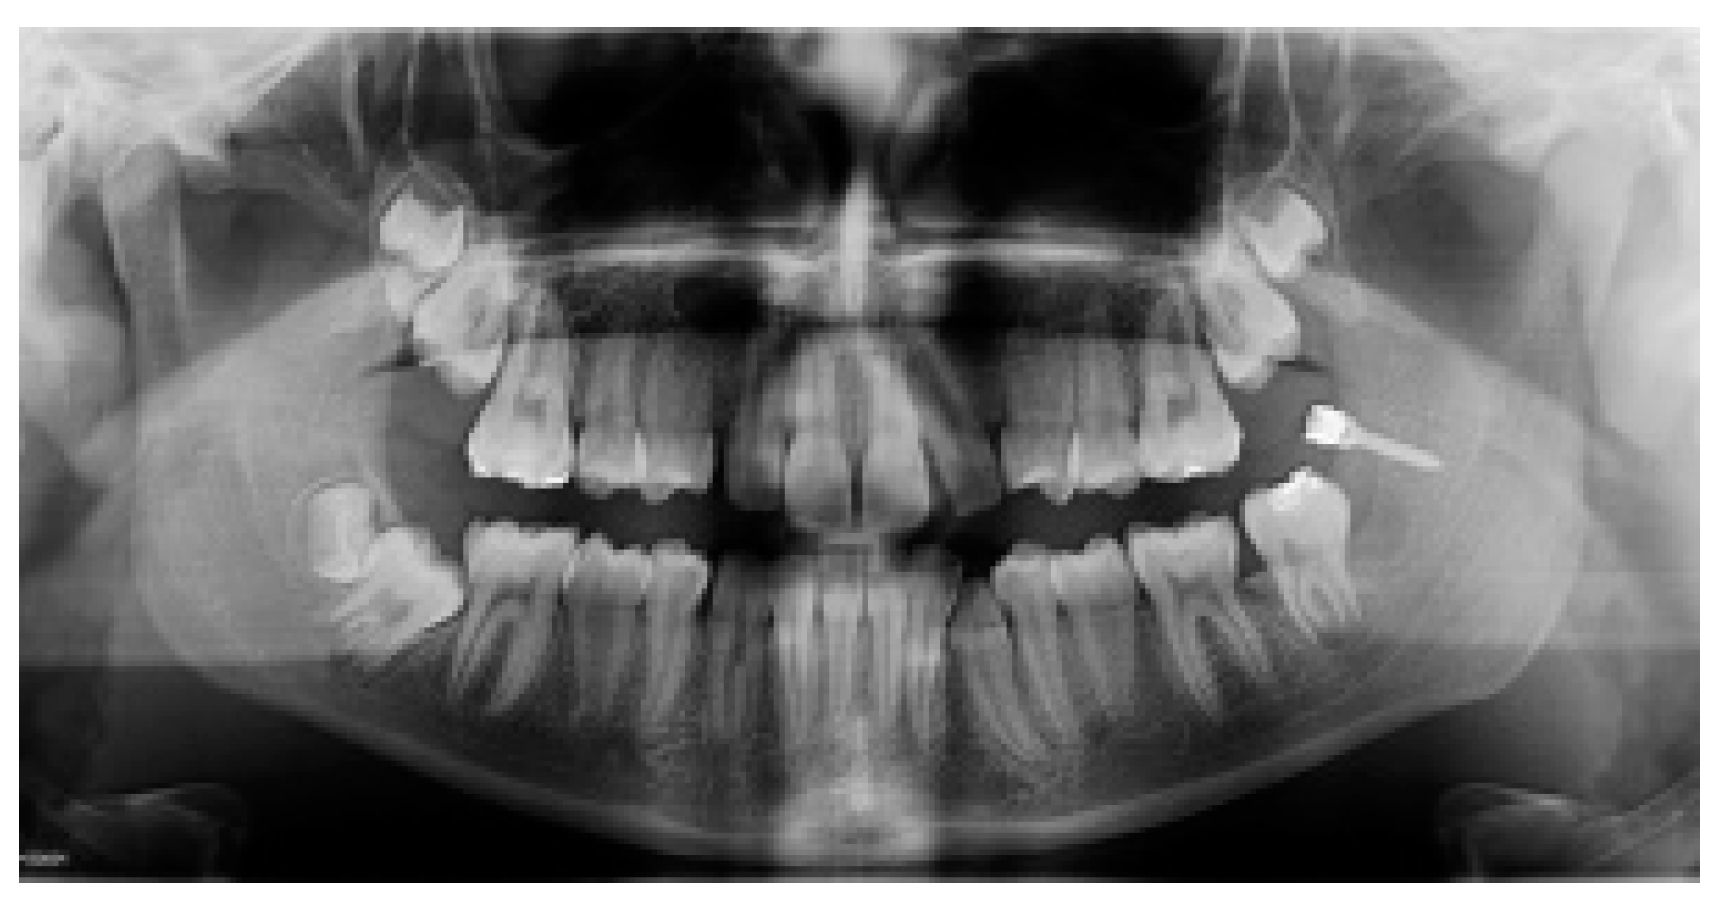

At the end of therapy the miniscrew was removed (Figure 4) and the other impacted MM2 was treated both with the same miniscrew and with the same orthodontic surgical procedure.

Figure 4.

(A,B) The elastic chain, brackets and (C) the miniscrew removal. (D) The final position in the arch of 3.7.